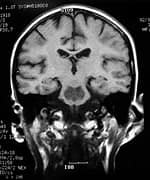

Traumatic brain injury (TBI) is often referred to as the "signature wound" of both the Iraq and Afghanistan wars. Traumatic brain injury occurs when a sudden trauma to the head disrupts brain function. In both these wars, however, even close proximity to the force of an explosion can be just as devastating. Most of the reported traumatic brain injury among Operation Enduring Freedom and Operation Iraqi Freedom veterans has been traced to improvised explosive devices, or IEDs. "Traumatic brain injury can be caused by a direct impact, or by acceleration alone," explains Dr. Mark L. Gordon, interventional endocrinologist and traumatic brain injury treatment specialist at Millennium Health Centers in Los Angeles. "Brain trauma also causes secondary injury, which takes place in the minutes and days following the injury," he adds. "These processes include alterations in cerebral blood flow and increased pressure within the skull, contributing substantially to damage from the initial injury." Gordon says traumatic brain injury can cause a host of physical, cognitive, emotional, and behavioral effects, some of which can be difficult to detect. Symptoms can appear immediately or weeks to years following the injury. "Insidious traumatic brain injury can be difficult to detect," Gordon says. "Localized damage to the frontal and occipital lobes occurs when the brain collides with the skull. Increasingly, we are discovering that traumatic brain injury is also a causative factor for accelerated hormonal deficiencies." These deficiencies, says Gordon, can cause a host of psychological, physiological, and physical manifestations, including depression, outbursts of anger, anxiety, mood swings, memory loss, inability to concentrate, learning disabilities, sleep deprivation, increased risk for heart attacks, strokes, high blood pressure, diabetes, loss of libido, menstrual irregularities, premature menopause, obesity, loss of lean body mass, muscular weakness, and a number of other medically documented conditions. What's more, Gordon points out that veterans suffering from these forms of psychological damage due to traumatic brain injury are frequently misdiagnosed and have their injury erroneously downgraded to post-traumatic stress disorder (PTSD). Moreover, especially in mild traumatic brain injury cases, symptoms at the initial time of injury may go unrecognized or unnoticed, but patients will still develop hormone deficiencies. Unfortunately, the government is slow to accept the link between traumatic brain injury and hormonal deficiencies. Dr. Gordon's Epiphany

By sheer serendipity, many years ago Dr. Gordon provided care for a young man with a history of numerous sports-related head injuries, whose parents were themselves patients at the clinic. The young man's symptoms long outlasted the immediate effects of his acute injury and included loss of concentration, memory, mental energy, focus, and physical well-being, often accompanied by loss of lean muscle mass and an increase in body fat. The parents, familiar with the effects of hormonal imbalances, naturally assumed that their son's problems might reflect an endocrine problem of his own. And indeed, many of his symptoms resembled those of adult patients with so-called hypopituitarism, or loss of pituitary gland function. The pituitary gland is located at the base of the brain and is sometimes called the "master" gland of the endocrine system, because it controls the functions of the other hormone- secreting glands. Gordon, who is nothing if not intellectually curious, hit the books. What he found was startling and life-changing, for himself as a clinician, for his young patient, and now for scores of additional victims of traumatic brain injury. Symptoms of Traumatic Brain Injury Mimic Pituitary DysfunctionDr. Gordon found a wealth of published literature suggesting that traumatic brain injury causes pituitary dysfunction, confirming his initial hunch.1 Although the figures vary between studies, at least 50% (and up to 76%) of traumatic brain injury victims show some loss of pituitary hormone function immediately after the brain injury.2-4 In general, the more severe the original brain injury, the more profound the hormonal deficits, although hormone deficiency or insufficiency (levels in the low "normal" range) are seen even in patients with mild traumatic brain injury.5-9 And while about 58% of patients recover their normal pituitary function within one year of their head injury, a shocking 52% develop new pituitary hormone deficiencies after one year. 10,11 Those deficits include reductions in many different pituitary hormones, including those that regulate the thyroid gland, the adrenal glands (that produce cortisol, DHEA, and other vital hormones), the gonads (where estrogen and testosterone are produced), and growth hormone.3,4,12,13 The severity of the hormone deficiencies correlates strongly with the kinds of symptoms Dr. Gordon was seeing in his patient. For example, patients with growth hormone deficiency or insufficiency had significantly worse disability rating scores, greater rates of depression, worse quality of life, lower energy, greater fatigue, and poorer emotional well-being, compared to brain injury patients with normal hormonal levels.14,15 Dr. Gordon's hunch was borne out: patients with traumatic brain injury often have pituitary hormone deficiencies or insufficiencies, especially in growth hormone. And those defects are closely associated with the persistent neurological, psychological, and emotional deficits that are so tragically common in survivors of traumatic brain injury. And where are you most likely to find a high concentration of survivors of traumatic brain injury? The United States military.